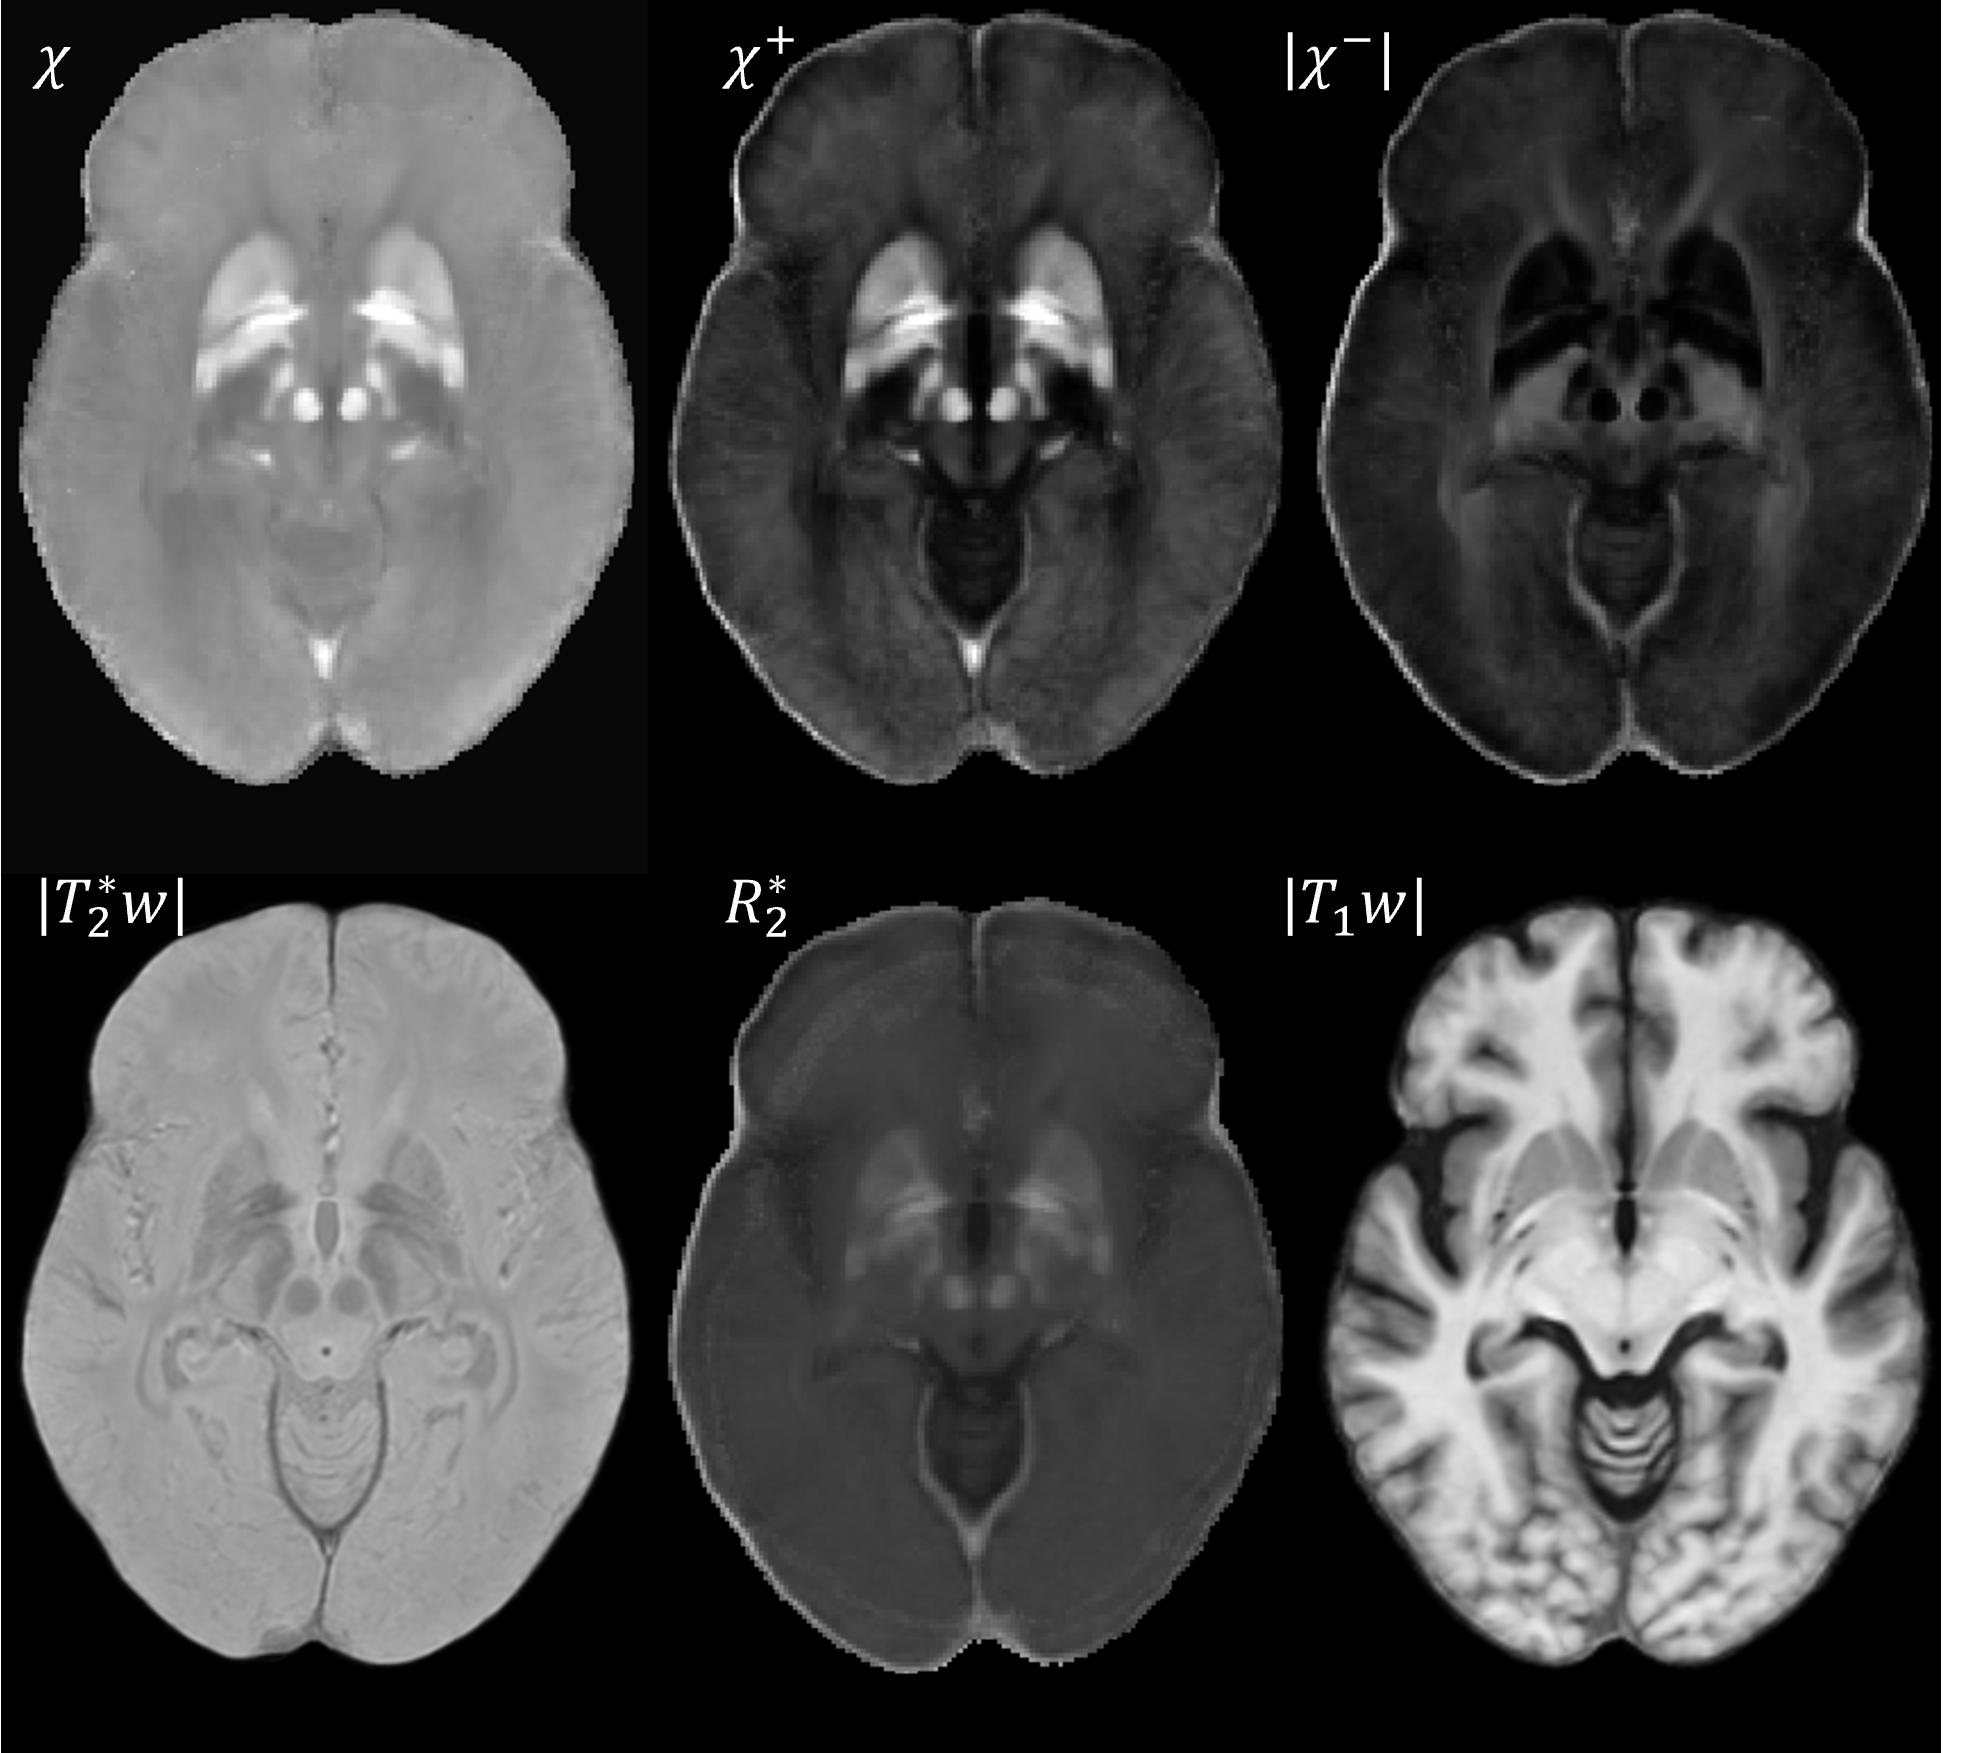

Results: The proposed atlas shows improvement over the McGill atlas in segmentations [figure2]. Applying transforms to relaxation and susceptibility map generates atlases in [fgure3]. The DN visualization, STN/SN delineation and GP/PUT contrast is improved in the susceptibility maps χ, χ+ [figure4] compared to structural T1w. White matter tracts on negative source χ– and myelin fraction v are visible [figure5].

Presented multi-contrast atlas.